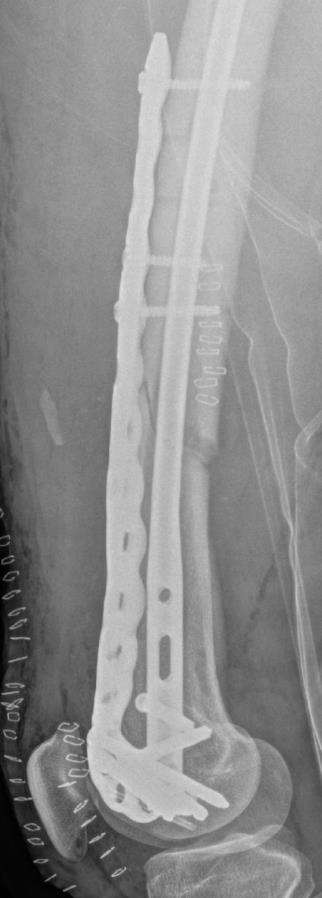

Summary Designed with SOMA (Stryker Orthopedics Modeling and Analytics) which includes a database with CT scans from hospitals across the world and state of the art algorithms that analyze shape variability, bone density, and implant fit Designed to link with the T2 Alpha Femur Retrograde Nail when using nail plate combination fixation Eight distal T20 screw holes, including 1 linking hole and 1 AP hole designed to capture Hoffa fragments Related Implants The Pangea® Femur Reconstruction System includes Lateral NPC Plate Medial NPC Plate (this topic) T2 Alpha™ Femur Retrograde Nailing System Design Tapered end allows for atraumatic submuscular insertion Staggered screw holes designed to enable surgeon to choose points of fixation and allows for placement of screws around an intramedullary implant or a prothesis AP hole screw hole trajectory that is designed to capture a "Hoffa Fragment" (Posterior Medial Condyle) Variable-angle screw holes circular universal holes accept non-locking screws, and locking screws within a 30° cone Proximal twist metadiaphyseal twist allows for screw placement anterior to posterior Linking hole designed to allow for seamless linking of the plate to a T2 Alpha Femur Retrograde Nail using an AlphaLink Dowel Indications Indications partial articular medial tibial plateau fractures medial plateau fragments in bicondylar tibial plateau fractures metaphyseal fractures epiphyseal fractures extra-articular proximal tibial fractures Contraindications active or suspected infection at the surgical site severe local inflammation around the operative area hypersensitivity or allergy to implant materials inadequate soft-tissue coverage over the implant Anatomy Osteology medial tibial plateau medial femoral condyle intercondylar eminence attachment point for cruciate ligaments tibial tuberosity insertion of the patellar tendon Muscles anteromedial tibia sartorius gracilis semitendinosus popliteus stabilizes and unlocks the knee Ligaments medial collateral ligament anterior cruciate ligament posterior cruciate ligament medial meniscus Approach Surgeons may use a standard medial, medial parapatellar, or medial subvastus approach to the distal medial femur Technical specifications Plate material type II anodized titanium (Ti6Al4V) Two plate lengths 155mm and 265mm Plate thickness 5mm Left and right anatomic options Screws Multiaxial locking 5.0 (14-120 mm) 4.0 (14-95mm) 5.0 (10-20mm) Cortex 4.5 (14-150mm) Cancellous 6.0 (20-150mm) 6.0 (30-150mm) 6.0 (45-150mm) Cable plug washer AlphaLink Dowel 50-90mm